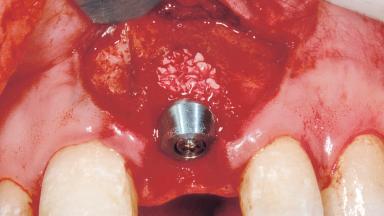

Immediate Placement of an Implant in a Maxillary Left Central Incisor Site

A 33-year-old female patient presented with an upper left central incisor that required extraction after a failed endodontic therapy. The tooth had been traumatized when the patient was a teenager and had undergone several endodontic treatments, including two apicectomy procedures. The patient was in good health and did not smoke. Clinical examination showed that the patient had a high lip line. In full smile, the gingival margins of the upper teeth were visible to the first molars. The gingival margins of central incisors 11 and 21 were only just showing. Examination of tooth 21 confirmed that the tooth was mobile and had hypererupted by 1 mm.

Bone Augmentation Horizontal|Simultaneous

Augmentation Materials Xenogenous|Membrane

Placement Protocol Immediate implant placement

Tooth Site Maxillary incisor or canine

Socket Morphology Single-root socket

Socket Integrity Damage to one or more bone walls

Bone Volume Damage to one or more socket walls